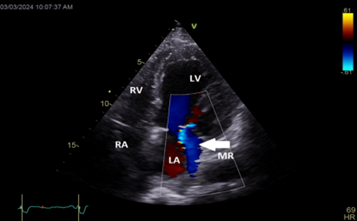

Color Doppler mapping of the mitral valve showed severe mitral regurgitation (MR) (Figure 4).

Figure 4: Apical long axis view still frame showing severe mitral regurgitation (white arrow)

LA=left atrium; LV=left ventricle; MR=mitral regurgitation

Color Doppler mapping of the mitral valve showed a decrease in MR severity with only grade I mitral regurgitation noted after correction of hypocalcemia (figure 8).

Figure 8: Apical 4 chambers view showing the decrease in mitral regurgitation severity (white arrow) after correction of hypocalcemia. LA=left atrium; LV=left ventricle; RA=right atrium; RV=right ventricle; MR=mitral regurgitation